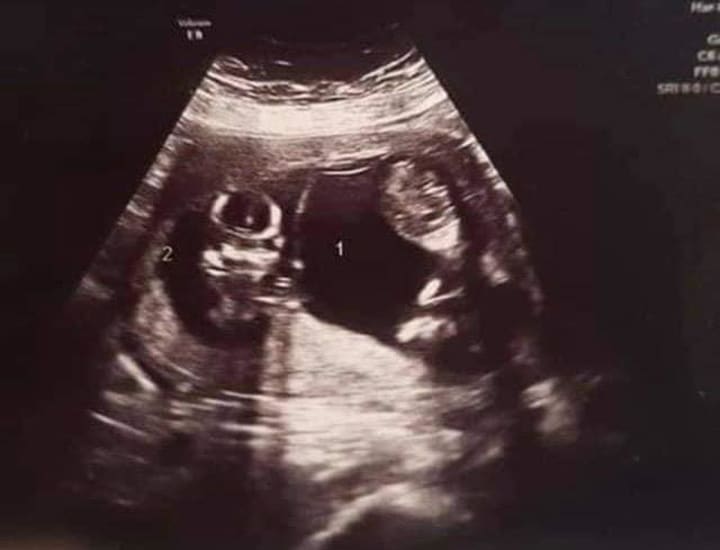

Two weeks later I had my first ultrasound. We were in for yet another surprise! Twins!

I woke the next morning to the sound of my husband sobbing. I lay in a pool of blood. Hemmoraging. Miscarrying. He sat beside the bed, clutching the ultrasound photos, and apologizing. I rolled over, burying my face in my pillow, and sobbed. I couldn't bear to even look at him.